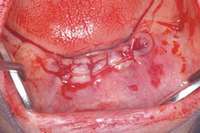

For patients on IV bisphosphonates, after bone is exposed, it is almost impossible to cover.15 Most cases worsen if surgical intervention is performed. Most patients must simply deal with the exposed bone and keep it clean so that bacterial infection does not occur. Figure 2 and Figure 3 show a postmetastatic prostate cancer patient with exposed bone. The treatment plan for this patient was to make a soft-lined denture that would not put pressure on the exposed bone and to check for bacterial infection on a routine basis. When dealing with patients on or about to begin IV bisphosphonate therapy, dentists need to be very astute. As stated earlier, this form of the drug has a much higher incidence of complications. These patients are often very sick and immuno-compromised and, therefore, must be managed properly. Pre-IV bisphosphonate patients (ie, those not yet receiving the drug) are much easier to manage than patients already receiving the drug. First, ask the treating physician, usually an oncologist, if he or she can wait 2 months before the drug is given. If the cancer is severe, it may not be possible to wait. Dentists should make use of whatever time can be made available before bisphosphonate treatment begins.16 This time should be used to get a full-mouth series of radiographs and to remove all dental infections, including all decay. If decay cannot be removed completely, the tooth should be considered for extraction. Before IV therapy begins, patients are at a lower risk for extraction complications than they are during bisphosphonate therapy.

Figure 2 and Figure 3 Postmetastatic cancer patient with BRONJ (A) in the lower right quadrant and (B) in the lower left quadrant.